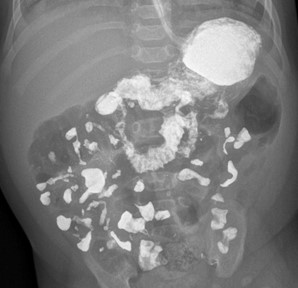

Дальнейшее обследование заключается в получении обзорных рентгенограмм органов брюшной полости в прямой проекции через 1, 3, 6, 9, 12 и 24 часа после введения контрастного препарата, их количество можно уменьшить более ранним завершением исследования, если эвакуация контраста ускорена (рис. 4). При неясной картине расположения петель кишечника добавляются снимки в косых проекциях, менее информативными считаются рентгенограммы в боковой проекции.

Рисунок 4 - Ребенок возрастом 2 месяца 10 дней, пассаж контрастного препарата

Примечание: рентгенограмма, полученная через час после введения контраста, положение лежа на спине, контрастный препарат поступил в тонкую кишку, визуализируется двенадцатиперстная кишка, дуоденоеюнальный переход расположен левее левой ножки позвонка, ниже пилоруса (норма)